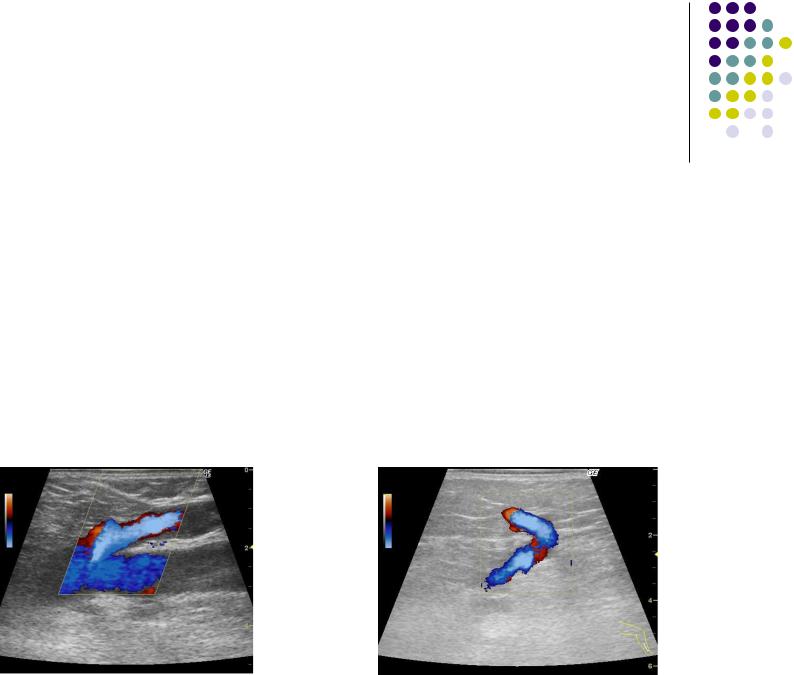

Ультразвуковые методы исследования венозного русла

Ультразвуковая допплерография применяется для общей характеристики состояния магистрального и коллатерального кровообращения.

Ультразвуковое ангиосканирование (дуплескное сканирование).

Метод позволяет определить наличие патологических рефлюксов по глубоким,поверхностным и перфорантным венам. Верифицирует наличие, границы и протяженность патологического процесса в вене (окклюзия, стеноз, тромбоз). Позволяет изучить структуру клапана.